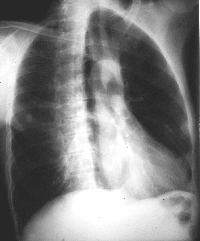

Standard cliche de

radiographie de face ( PA ) et de profile gauche du

poumon .en position debout |

Avec les deux cliches OAG et OAD a angle

precedent , on peut detecter la lesion marquee en outre de

l'ombre du coeur et de la colonne vertebrale . Et par la meme

technique ,

quelques courbures de la silhouette du coeur avaient aussi detecte ... |